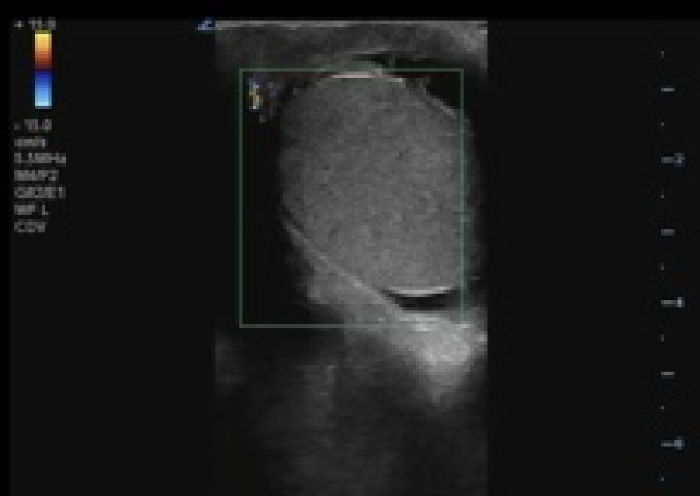

In your first image (Image 1), you realize there is no flow with color Doppler. Additionally, you find a torsed cord complex (Image 2), also known as the “corkscrew sign.” You consult Urology who is busy in the operating room with another case. You decide to perform a manual detorsion due to your concern for testicular atrophy and risk of infertility. Using the open book technique, you get relief of pain and return of vertical positioning of the testicle after two rotations. On your repeat testicular POCUS with color Doppler you obtain these images (Images 3 and 4), which demonstrate venous and arterial flow throughout the testicle. The cord is now untwisted and appears linear in orientation.

Torsion - image 3_crop.pngImage 3. Color Doppler demonstrating intratesticular flow toward and away from the probe.